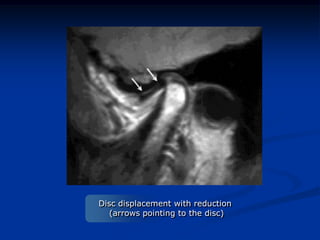

MRI imaging using Sigma

(General Electric Co. Wisconsin) machine

Disc displacement with reduction

(arrows pointing to the disc)